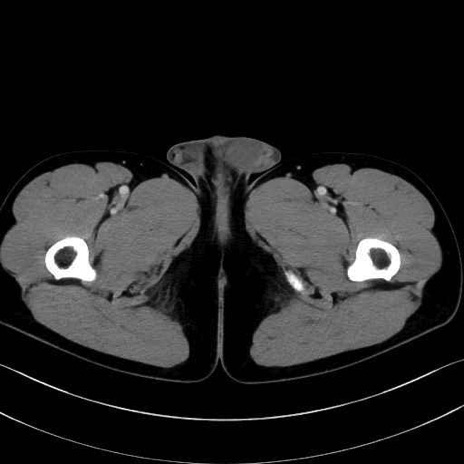

精嚢(seminal vesicle)のCT画像における解剖

症例

【症例】20歳代 男性 スクリーニング